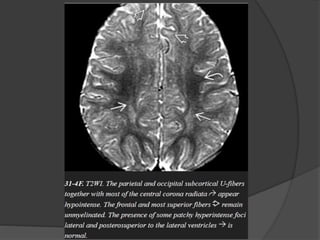

Three month  Cerebellarfolia.  Ventral brainstem.  Optic radiation.  Anterior limb of internal capsule.  Occipital subcortical U fibers.  Corpus callosum splenium. Six month  Corpus callosum genu.  Paracentral subcortical U fibers.  Centrum semioval ( Partial ).

Eight month  Centrumsemiovale ( complete except frontoteporal area ).  Subcortical U fibers ( complete except most rostral frontal area ). Eighteen month  Essentially like adult.

Myelination milestones after birth T1WI 3 m cerebellar white matter  4 m corpus callosum splenium  6 m corpus callosum genu T2WI  6 m corpus callosum splenium  8 m corpus callosum genu  11 m anterior limb internal capsule  14 m frontal white matter